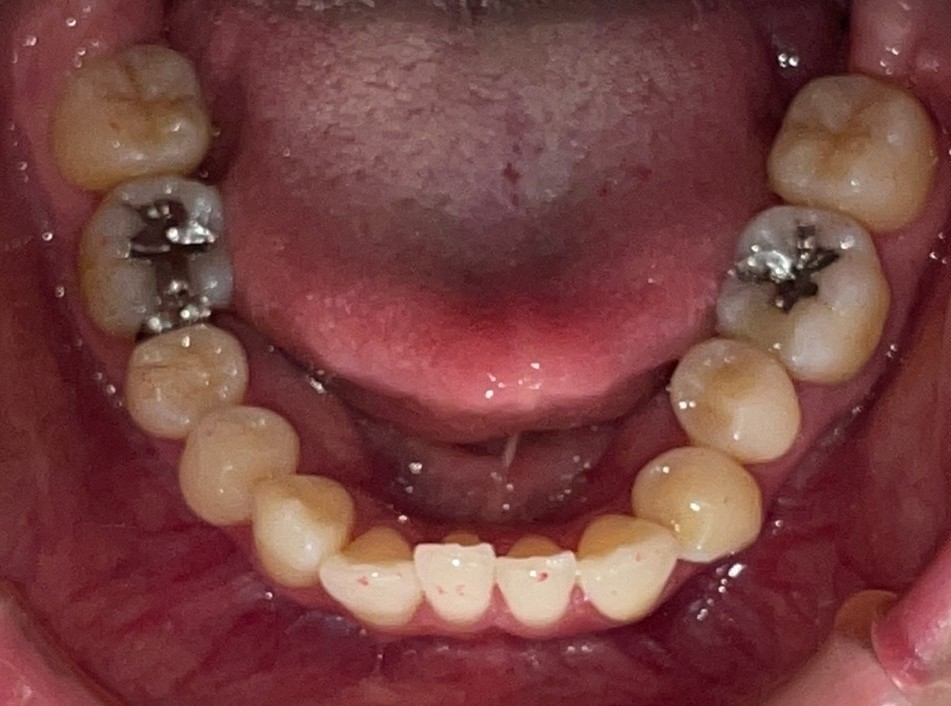

Before

After

矯正の種類 / invisalign GO

年齢・性別 / 50代女性

主訴  /  叢生 交叉咬合

治療期間 / 17ヶ月

費用 / 簡易検査 5,000円(税別) 精密検査 30,000円(税別)

両額マウスピース 450,000円(税別)  両額リテイナー料 60,000円(税別)

※マウスピース交換時別途調節料3,000円(税別)

副作用 / 口内炎・歯の移動に伴う痛み・知覚過敏 ※数日で収まる場合が多いです

リスク / 後戻り防止の為、夜のみマウスピースで保定を指示